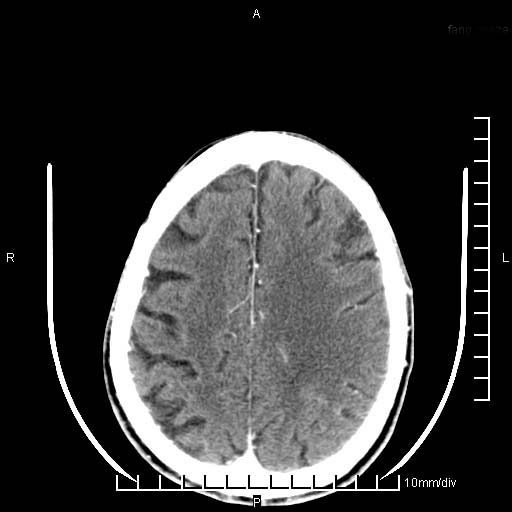

临床以双下肢浮肿,疼痛收治,无明显神经系统症状,既往无梗塞,出血病史。左颞叶见低密度灶,考虑什么?

考虑左侧颞叶脑软化灶。

无强化 无占位 软化灶吧

无强化、 无占位、局部脑沟增宽, 软化灶吧。